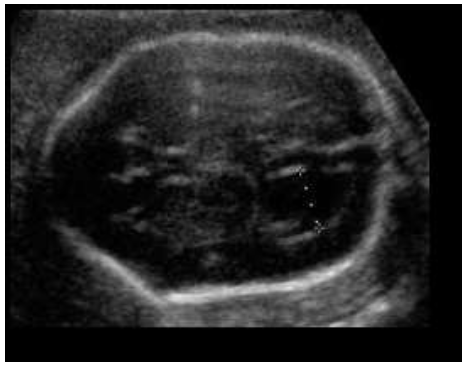

Paciente 24 anos, secundigesta, apresentando idade gestacional de 23 semanas, gestação não planejada, encaminhada para avaliação morfológica do segundo trimestre.

Após analisar as imagens abaixo, quais os sinais ecográficos encontrados e qual a hipótese diagnóstica?